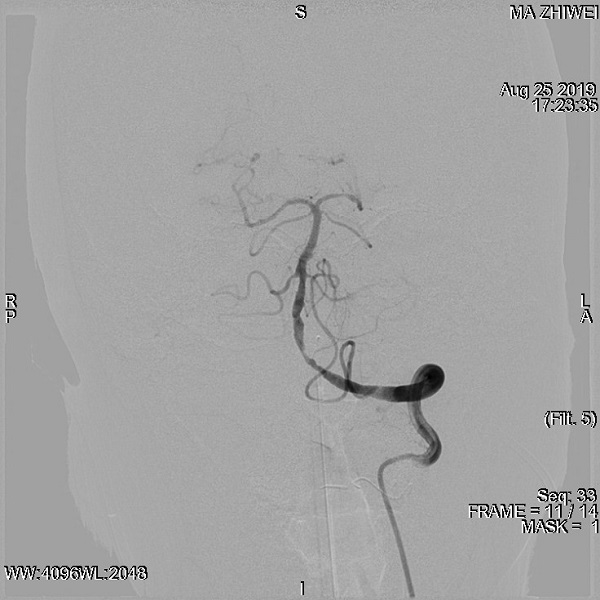

医院脑血管介入中心主任、危急重症医学科副主任、主任医师刘叶辉教授综合评估后考虑患者为急性大动脉闭塞,已经错过最佳静脉溶栓时间,患者随时可能因脑干、小脑梗死而死亡,与家属沟通后决定行介入取栓治疗。完善脑血管检查提示,左侧椎动脉起始部重度狭窄,右侧椎动脉发出大脑后下动脉以远闭塞。

予以“球囊扩张+支架植入+机械取栓”术后血管再通成功,左侧椎动脉起始部重度狭窄明显改善。